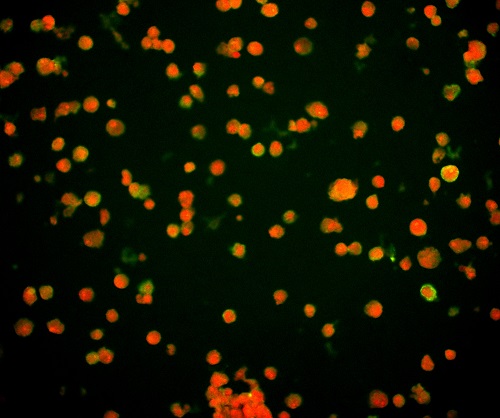

(1)通過(guò)觀測(cè)對(duì)病毒進(jìn)行特異性標(biāo)記產(chǎn)生的熒光信號(hào),從而實(shí)現(xiàn)對(duì)病毒位置數(shù)量的判斷。病毒主要由核酸和蛋白質(zhì)組成,常見(jiàn)的一種方法是利用熒光標(biāo)記的特異核酸探針與病毒含有的靶DNA分子或RNA分子進(jìn)行雜交,可通過(guò)在熒光顯微鏡下觀察熒光信號(hào),來(lái)確定與特異探針雜交后被染色的病毒的分布和數(shù)量,這種方式也稱為原位熒光雜交技術(shù)(FISH)。

FISH做的病毒檢測(cè),紅色為病毒外殼蛋白

(引自公開論文https://doi.org/10.1073/pnas.1820132117)